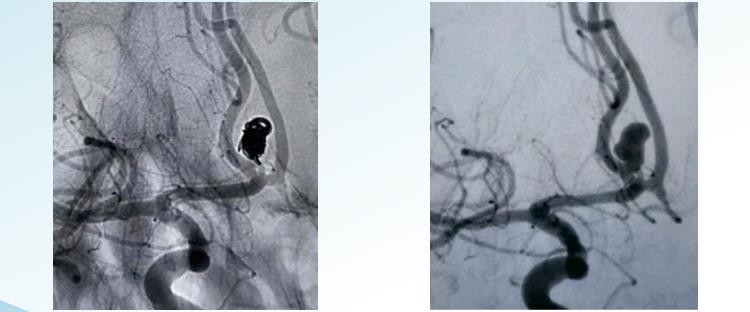

Đổi mớiTMHệ thống cuộn dây phình động mạch có thể tháo rời cung cấp các tùy chọn ngẫu nhiên, xoắn ốc và 3D có thể tháo rời để gây tắc mạch nội mạch với đường kính từ 1 đến 22 m. Nó được thiết kế để làm thuyên tắc chứng phình động mạch từ khung đến phần cuối và bao gồm các cuộn dây được tạo hình đặc biệt để làm đầy chỗ phình động mạch đồng tâm và các cuộn dây có thể tích lớn để đạt được mật độ bó kín cao. Cuộn dây ngẫu nhiên là hình thức đơn giản nhất và lâu đời nhất của kỹ thuật cuộn dây phình động mạch. Nó liên quan đến việc chèn một cuộn dây hoặc một nhóm cuộn dây vào chỗ phình động mạch. Các cuộn dây thường được làm bằng bạch kim, mỏng và cuộn chặt để ngăn chặn bất kỳ khoảng trống hoặc khoảng trống nào hình thành trong túi. Cuộn xoắn ốc liên quan đến việc sử dụng một sợi dây mỏng và dài hơn được cuộn quanh chính nó theo kiểu xoắn ốc, tạo thành một cấu trúc giống như lò xo. Dây được đưa vào túi phình động mạch ở dạng thẳng và khi vào bên trong, nó được phép cuộn lại và nở ra để lấp đầy túi phình động mạch. Các cuộn dây xoắn ốc rộng hơn và được bó chặt hơn so với các cuộn dây ngẫu nhiên, do đó mang lại khả năng tắc nghẽn chứng phình động mạch tốt hơn. Cuộn dây 3D liên quan đến việc sử dụng một cuộn dây được thiết kế tùy chỉnh, được tạo ra bằng cách sử dụng quy trình chụp ảnh trên máy vi tính để tạo ra mô hình ba chiều chính xác của chứng phình động mạch. Cuộn dây được sản xuất để phù hợp với kích thước và hình dạng chính xác của chứng phình động mạch. Loại cuộn dây này được thiết kế vừa khít với túi phình động mạch, mang lại khả năng tắc tuyệt vời và giảm nguy cơ biến chứng.. 3Cuộn dây D đặc biệt hiệu quả trong điều trị chứng phình động mạch khó tiếp cận hoặc trong các mạch máu mỏng manh.

5. Đóng khung chắc chắn, lấp đầy đồng đều và hoàn thiện bằng cách tìm kiếm các khoảng trống trong chỗ phình động mạch.